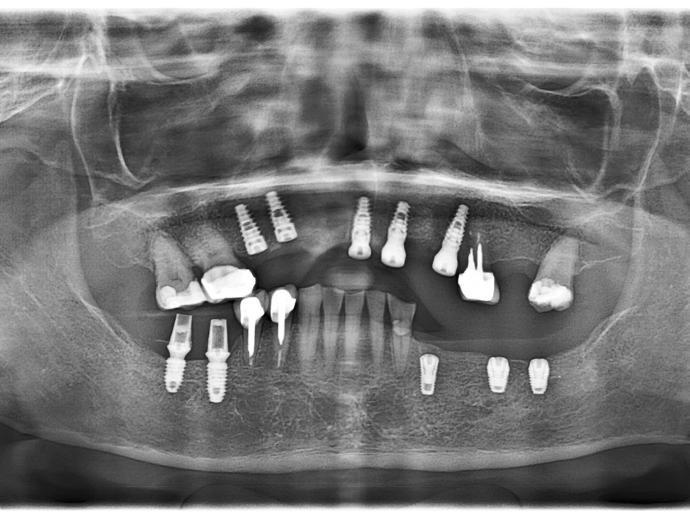

智能AI模擬,上顎前牙、下顎兩側後牙均缺牙

植入植體